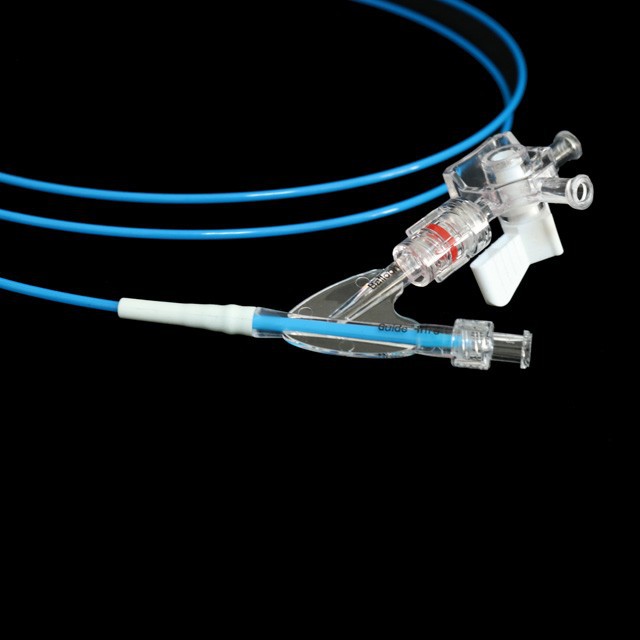

And તે એન્ડોસ્કોપ્સ હેઠળ પાચક ટ્રેક્ટ કડકતાના વિક્ષેપ કામગીરીમાં પુખ્ત વયના અને કિશોરો માટે યોગ્ય છે .}

● ઝડપી ડ્રેનેજ ડિઝાઇન સર્જરીનો સમય ઘટાડવામાં મદદ કરે છે .

The ટ્યુબની શ્રેષ્ઠ ડિઝાઇન તેને સરળ અને સારી સ્થિતિસ્થાપકતા, મજબૂત વળી જતું પ્રતિકાર અને સરળ પસારતા બનાવે છે .

● પ્રી-ઇનપુટ 0 . 035 "સોફ્ટ ટીપ અને માર્ક સાથે માર્ગદર્શિકા વાયર, જે અંદરના માર્ગદર્શિકા વાયરની લંબાઈનો અંદાજ કા .વા માટે સરળ છે.